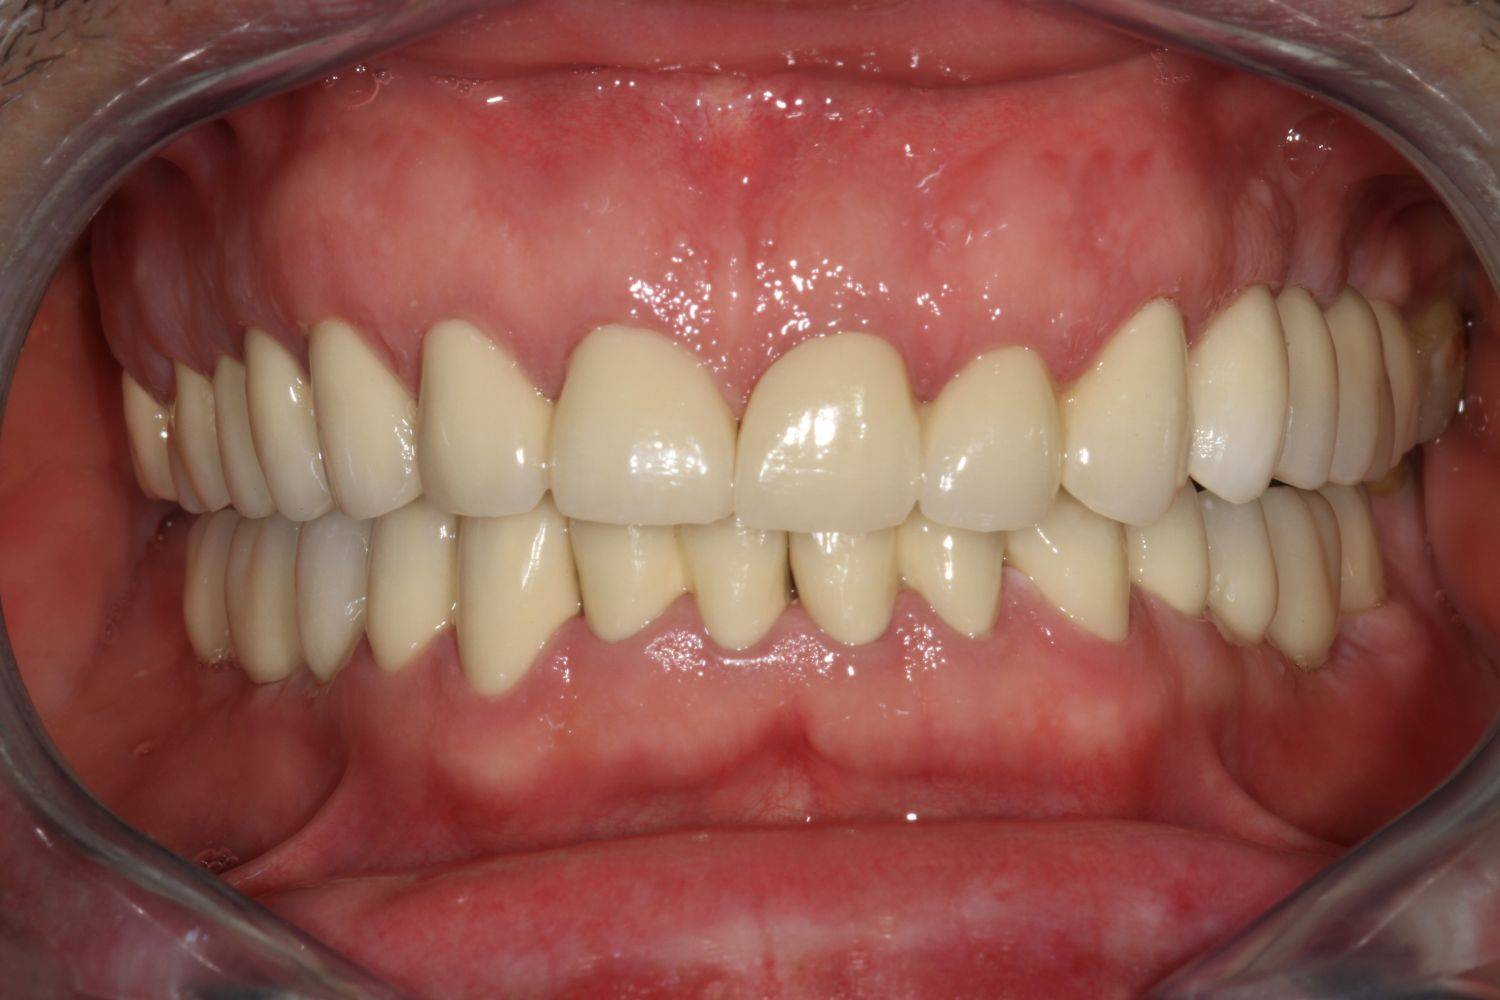

6. Eset

Nagymértékű fogkopás, erózió, csikorgatás a teljes rágóapparátust túlterhelve okoz reménytelennek tűnő helyzeteket.

Ebben az esetben implantátumok , koronák és hidak segítségével változtattunk a páciens fogainak érintkezésén. 6 hónapig ideiglenes hidakkal teszteltük a megváltoztatott harapási pozíciót. Ezután készültek el a végleges fix pótlások.